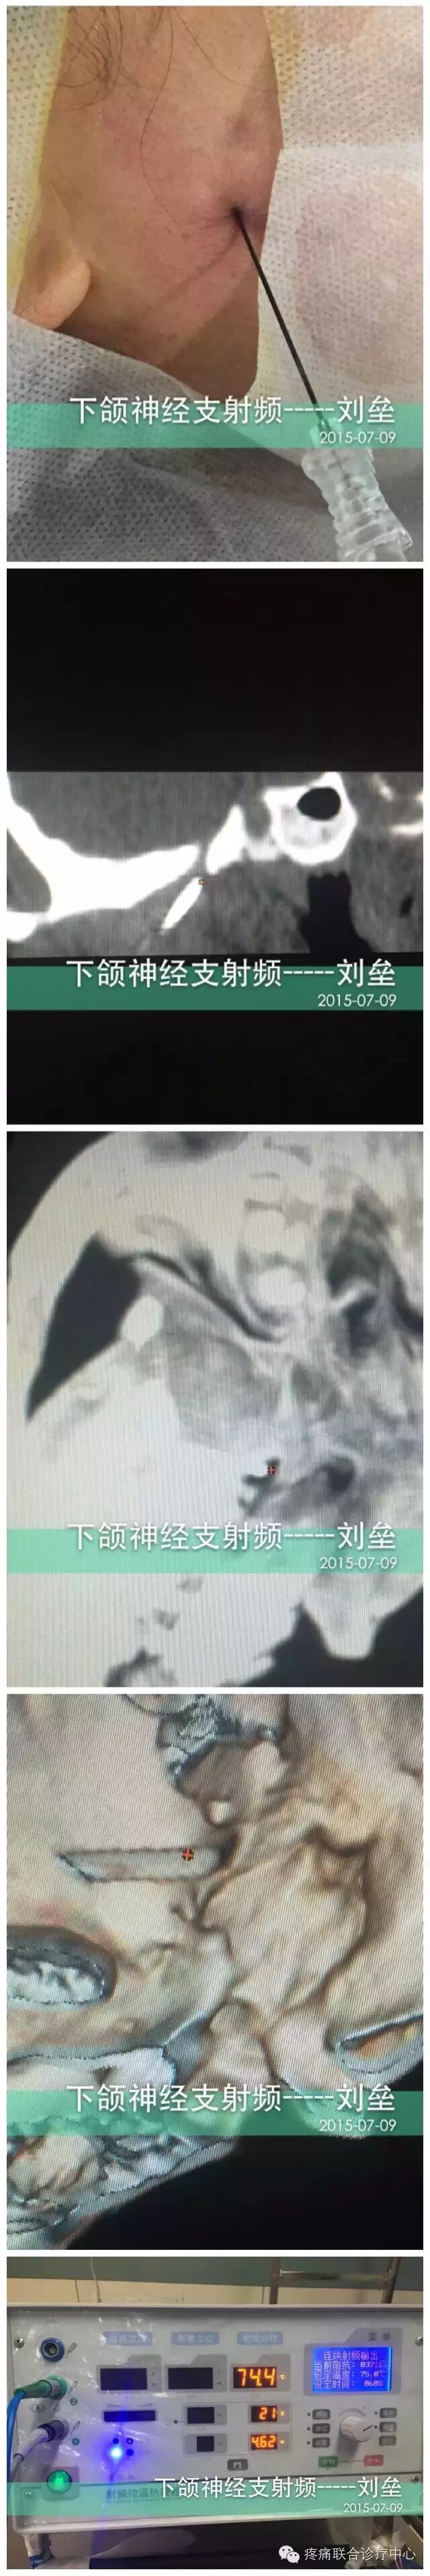

术前完善血尿常规、凝血四项、心电图、血糖、肝肾功能等检查,术前半小时肌注硫酸阿托品注射液0.5 mg,术中静注抗生素以预防感染。患者取仰卧位,头稍后仰。监测心电、血压等变化。背部贴附射频仪的负极板。患侧面颊部,局部消毒铺巾。局麻后,采用Hartel前入路穿刺方法[2.3、6、7]。穿刺点位于患者口角外下2.5cm(A点)、患侧外耳道前结节B点及同侧瞳孔位置(C点),三点做AB及AC连线与面部垂直的两个平面的交线即是穿刺进针的方向。当穿刺针到达卵圆孔部位,在C形臂X线机投照或CT导向下,取颏斜位,增强器向头端旋转30°~35°,向健侧旋转15°~20°可显露出患侧卵圆孔,进针6.0~8.5cm深度时,刺入Meckel囊时有突破感。射频电极自动测量阻抗一般为250~360Ω。若穿刺针进入Meckel囊可见脑脊液流出,此时应将穿刺针后退2~3mm。然后分别进行感觉和运动功能的方波电流刺激并采用电生理监测验证电极位置。术中C形臂定位(图1、2);CT定位(图3、4)。靶点准确定位后进行射频治疗[3、8]。为了达到手术操作无痛,术中常规使用丙泊酚1~2 mg/kg静脉麻醉,并可在术中唤醒患者,以检查面部皮肤痛觉减退的范围。若病变累及多个部位者,宜进一步行相应周围支的射频热凝治疗[3.9]。术后卧床4h,应用抗生素2d。一般术后2~3天症状消失出院。